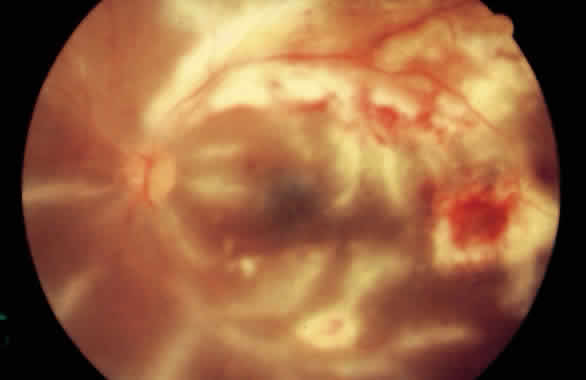

chorioretinitis accompany the vasculitis. PERIPHLEBITIS AND PHLEBITIS Venous inflammation is much more common than arteritis. Early venous changes include patchy dilatation, venous irregularity, and perivenous cuffing. These cuffs are made up of white blood cells and vary greatly in density, from minimal obscuration of a vein to complete concealment of the blood column without occlusion. Vitreous cells may be present over the vessels. Vascular sheathing appears as white lines along the vein walls and may result in venous flow impedance and vein occlusion (Figs. 1 and 2).25 It may be clinically difficult to distinguish perivenous inflammation from true phlebitis. Any vein from the optic nerve head to the peripheral retina is susceptible.

If inflammation is prolonged, secondary changes such as thickening of the vein wall and endothelial cell proliferation may occur. These can lead to narrowing and obstruction of the lumen, thrombosis, and necrosis. Other late changes secondary to vascular occlusion include telangiectasia, microaneurysms, and neovascularization.21 Histopathologically, polymorphonuclear leukocytes are the predominant cell type early in the disease, but lymphocytes accompanied by an occasional plasma cell, giant cell, or epithelioid cell become the predominant cell types later in the disease.25 Fluorescein angiography often reveals focal areas of staining or dye leakage even before ophthalmoscopically visible signs are present (Fig. 3). In advanced cases of periphlebitis, angiography may show diffuse leakage of dye from retinal veins and capillaries.26

EALES' DISEASE Eales' disease was initially described as recurrent retinal and vitreal hemorrhages, epistaxis, constipation, and headaches in young men.34 It has since been redefined as an idiopathic obliterative peripheral retinovasculopathy with variable degrees of nonperfusion, vascular sheathing, retinal vascular abnormalities, peripheral retinal neovascularization, and hemorrhage (Fig. 6).35 It usually affects men in the third decade of life and is bilateral in up to 90% of cases.36 Many patients are symptomatic in only one eye, but fundus examination of the fellow eye may reveal early changes such as periphlebitis, vascular sheathing, and peripheral retinal nonperfusion.37 The presenting symptom in 90% of patients is a painless blurring of vision, often due to vitreous hemorrhage.36

The clinical manifestations of Eales' disease result from three basic pathologic changes: inflammation, ischemia, and neovascularization.38 Vitreous cells are present and anterior segment inflammation is variable. In early stages, venous dilatation and tortuosity are seen in the periphery.37 Accumulation of exudate around peripheral retinal venules appears as thin white lines parallel to the blood column and can obscure the vessel. Areas of vascular sheathing frequently leak fluorescein dye; however, the sheathing does not always correspond to the staining, nor is the amount of leakage proportional to the activity of the inflammation.37 Progression of Eales' disease results in widespread venous occlusion, perivenular or arteriolar exudation, extensive sheathing, and retinal hemorrhage. Involved vessels become obliterated and avascular areas develop in the periphery. The junction between nonperfused and perfused retina is usually sharply demarcated.37 Vascular abnormalities seen at this junction include microaneurysms, venovenous shunts, venous beading, hard exudates, and cotton-wool spots.39,40 Obliteration of peripheral venules and arterioles and branch retinal vein occlusions can be confirmed angiographically.41 Capillary nonperfusion leads to peripheral and disc neovascularization; this is observed in up to 80% of patients with Eales' disease37 and contributes to the development of fibrous proliferation and the risk of retinal detachment. Peripheral neovascularization is more common and is frequently located at the junction between perfused and nonperfused retina. Bleeding from damaged or abnormal vessels may result in vitreous hemorrhage. Extension of nonperfusion into the posterior pole may result in decreased visual acuity due to macular edema or epiretinal membrane or macular hole formation. Some patients develop anterior uveitis, cataracts, rubeosis iridis, secondary neovascular glaucoma, and optic atrophy in the late stages of the disease.37 There is histopathologic evidence of lymphocytic and granulomatous infiltration of vessel walls and lumina, and perivascular spaces.42 The cause of Eales' disease, however, is unknown. It may represent a hypersensitivity reaction to tuberculoprotein. This hypothesis stems from isolated reports of vasculitis after skin testing or BCG vaccine and the prevalence of positive purified protein derivative testing in patients with the disease.43 Tubercles in the venous walls were also reported in the older literature.44 One study found elevated IgA and IgG levels in patients with Eales' disease,45 whereas other studies showed no immunoglobulin abnormality.46,47 Abnormal levels of circulating immune complexes have also been reported.48 Eales' disease probably has more than one cause. IDIOPATHIC RETINAL VASCULITIS Retinal vasculitis occurring in isolation, with no systemic association, has been referred to as idiopathic retinal vasculitis.49 Typical findings include inflammatory cells in the vitreous and sheathing of retinal veins and postcapillary venules. Fluorescein angiography may show diffuse capillary leakage.50 Idiopathic retinal vasculitis can be classified into ischemic and nonischemic forms. Patients with ischemic retinal vasculitis have a worse visual outcome despite aggressive systemic treatment than those with nonischemic retinal vasculitis.49 A few patients with idiopathic retinal vasculitis have disseminated central nervous system lesions characteristic of multiple sclerosis.50 Lyme disease and cat scratch disease (Bartonella henselae) have been anecdotally associated with retinal vasculitis.51–53 OPTIC DISC VASCULITIS Optic disc vasculitis (papillophlebitis) is a unilateral, idiopathic, usually benign condition that primarily affects healthy adults younger than 40.54 The only symptom is blurred vision. Retinal findings include edema of the optic disc and adjacent retina, markedly dilated and tortuous retinal veins with minimal arterial involvement, and a variable amount of retinal hemorrhage (Fig. 7). Other findings include venous sheathing, retinociliary shunt vessels, and depigmentation of the macular area.55 Vitreous cells are absent or scant. Fluorescein angiography findings may include delayed venous filling, marked retinal venous dilatation, and massive dye leakage from the optic nerve head and large retinal veins.54 Hayreh divided the disease into two types: type 1, with optic disc edema and good visual outcome as the dominant features, and type 2, with a clinical picture similar to central retinal vein occlusion.54 In the second type, the visual outcome depends on the site and extent of the lesion. Hayreh suggested that type 1 is due to a mild nonspecific vasculitis of the ciliary vessels, whereas type 2 is probably due to phlebitis of the central retinal vein within the optic nerve head or retrolaminar region.54 Papillophlebitis is self-limited, lasting 6 to 18 months, and the visual acuity is seldom severely decreased. Unlike peripheral retinal vasculitis (Eales' disease), optic disc vasculitis is rarely recurrent or associated with vitreous hemorrhage. No therapy is necessary, although corticosteroids have been reported to shorten the course. There is controversy over the existence of papillophlebitis, and some believe it represents a mild central retinal vein occlusion in a young person.56 INTERMEDIATE UVEITIS Intermediate uveitis is a syndrome with a noninflamed external eye, low-grade anterior segment reaction without synechia formation, and vitreous inflammation. Mild periphlebitis and optic disc and macular edema may also occur. Intermediate uveitis includes “pars planitis” and conditions that have been previously called chronic cyclitis, vitritis, and peripheral uveitis. This syndrome has been associated with several systemic diseases, including multiple sclerosis, Whipple's disease, and reticulum cell sarcoma.57 Pars planitis is associated with the HLA-DR2 antigen and the temporal development of multiple sclerosis.23 Pars planitis, the classic intermediate uveitis that usually occurs in young people, is distinguished by the presence of whitish gray cellular exudate (snowbanking) over the inferior pars plana. Retinal vascular involvement has been reported in 13% to 77% of cases of pars planitis.58,59 Peripheral retinal veins appear dilated, segmented, and tortuous, some with vascular sheathing. Retinal vascular leakage is common and was found in 79% of fluorescein angiograms in one study.60 Patchy perivenous staining in the posterior pole may accompany the closely spaced spots of fluorescein stain along peripheral venules. Arterial involvement has been reported infrequently.61 Although the natural course is usually one of chronic smoldering inflammation, vein occlusions, peripheral and disc neovascularization, vitreous hemorrhage, and retinal detachment have been observed.61,62 Histopathologic examination reveals thickening of the vessel wall and perivascular round cell cuffing.63 These changes can be observed as far posteriorly as the optic nerve. ACUTE RETINAL NECROSIS Acute retinal necrosis is predominantly a fulminant retinitis with an associated obliterative vasculitis of the retina, uvea, and optic nerve.64 Acute retinal necrosis is characterized by panuveitis, vitritis, vaso-occlusive retinal arteritis, and necrotizing retinitis.65 Vitreous haze often makes fundus examination difficult, but frequently arteriolar occlusions can be seen associated with these areas of white retina. There is an abrupt border between normal and abnormal retina, suggestive of an ischemic process. Progression results in retinal artery narrowing and sheathing. Perivenous sheathing and intraretinal hemorrhage may also be present. Angiographically, there is arteriolar obliteration and absence of capillary perfusion in affected areas, as well as dye leakage and vessel wall staining in the late phase. Electron microscopy, immunohistochemical techniques, and viral culture studies implicate members of the herpesvirus family in the genesis of acute retinal necrosis.66–70 FROSTED BRANCH ANGIITIS Frosted branch angiitis, an inflammatory condition of unknown origin, is characterized by widespread periphlebitis with intraretinal hemorrhage in otherwise healthy patients. It is an acute condition and may be unilateral or bilateral. Fundus examinations reveal severe white sheathing of retinal vessels, resembling frosted tree branches. Although both arteries and veins may be involved, the venules tend to be more commonly affected. The inflammatory exudates around retinal vessels may be related to deposition of antigen-antibody complexes.71,72 Anterior chamber and vitreous inflammation may be seen. On fluorescein angiography, there is late staining and dye leakage with no evidence of stasis or occlusions.21 Frosted branch angiitis has also been reported in patents with cytomegalovirus retinitis (Fig. 8).73 IDIOPATHIC RETINAL VASCULITIS, ANEURYSMS, AND NEURORETINITIS Idiopathic retinal vasculitis, aneurysms, and neuroretinitis syndrome usually affects young, healthy persons and has a slight female predominance.74 There are no systemic abnormalities. Retinal findings include dilatation of the retinal and optic nerve head arterioles, vasculitis, neuroretinitis, and extensive peripheral capillary nonperfusion. Retinal neovascularization, optic nerve head swelling, and anterior uveitis can occur. Systemic corticosteroids have little effect on the progression of the disease.74 |